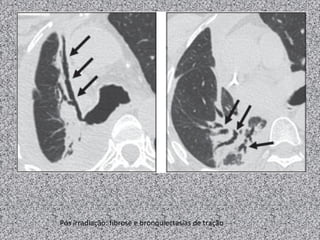

Pós irradiação: fibrose e bronquiectasias de tração

Pós irradiação: fibrosee bronquiectasias de tração